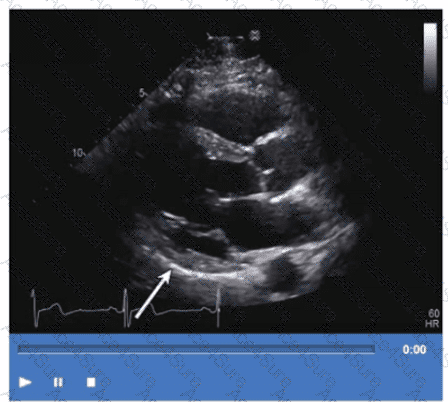

The apical two-chamber echocardiographic view displays the inferolateral wall (also called posterior lateral). The arrow points to this inferolateral segment, which is located inferiorly and laterally in the left ventricle.

Anteroseptum and inferoseptum relate to the interventricular septum, while anterolateral is the anterior lateral wall, opposite the inferolateral wall. Correct regional wall motion assessment is essential for ischemic disease evaluation.